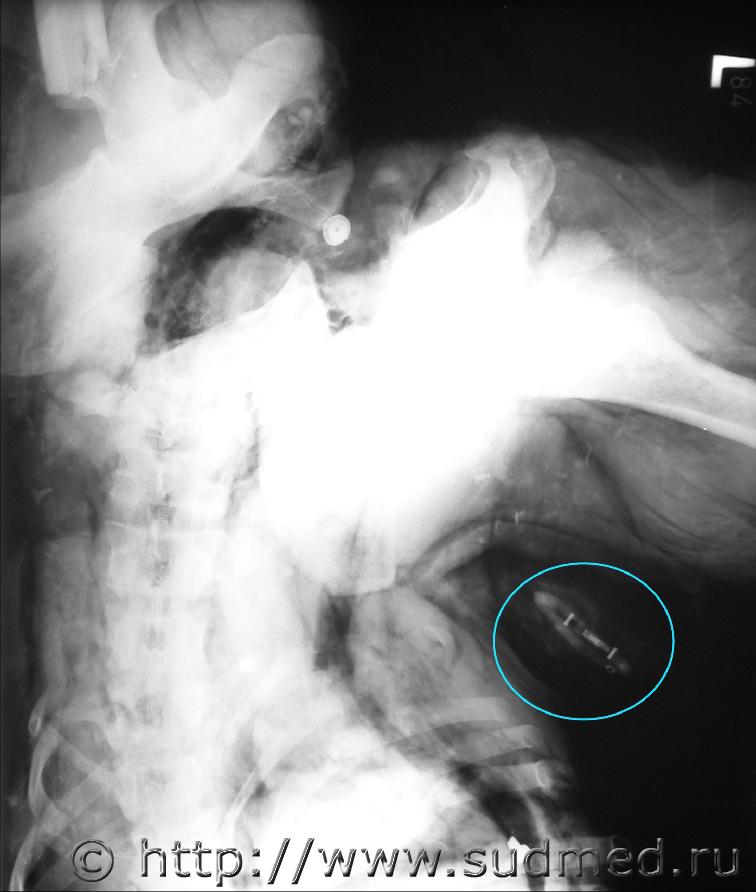

Мой случай - после катастрофы самолета АН-24 с военнослужащими, которые возвращались с миссии KFOR в Косово. Подробности - тут

Перед вскрытием делались рентгеновские снимки всех трупов (большей частью обгоревших и обугленных). В этом случае в размозженных тканях левой поясничной области был найден электрический предохранитель с плавкой вставкой, пронумерованный (на негативном Ro-снимке - в кружке). По его спецификации потом определили, что погибший вероятно сидел в хвостовой части салона самолета при столкновении с землей.